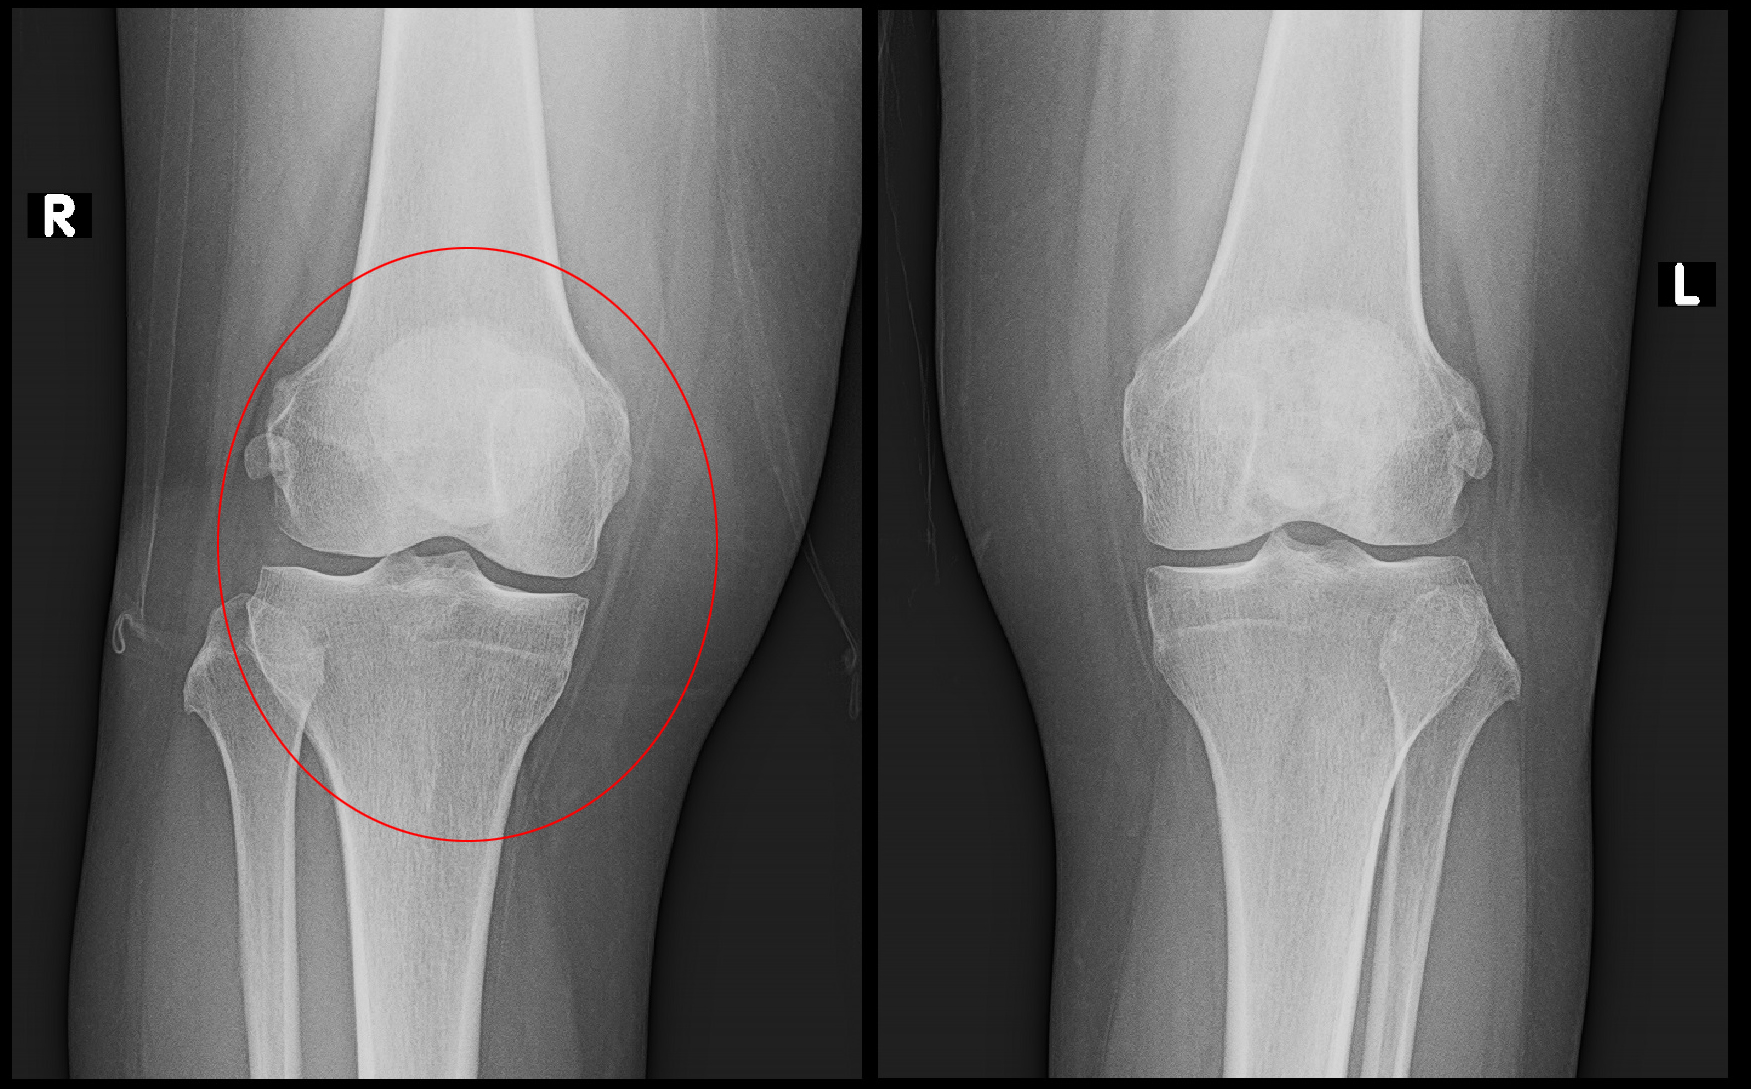

両膝MR画像

変形性膝関節症の初期であれば、このMRI画像で右膝の内側(赤枠の領域)に白く炎症所見が確認されて良いのですが、それが見られません。

他の検査条件でも、他整形外科で診断された内側半月板の損傷の所見も含め、異常所見は何一つありませんでした。

そうなるとこの患者さんの膝痛の原因は膝にはないということになります。

そのような場合、痛みの原因で最も可能性が高いのは腰(腰椎)で、腰に起因する坐骨神経痛の一つの症状として膝痛が出ているという状態が疑われます。